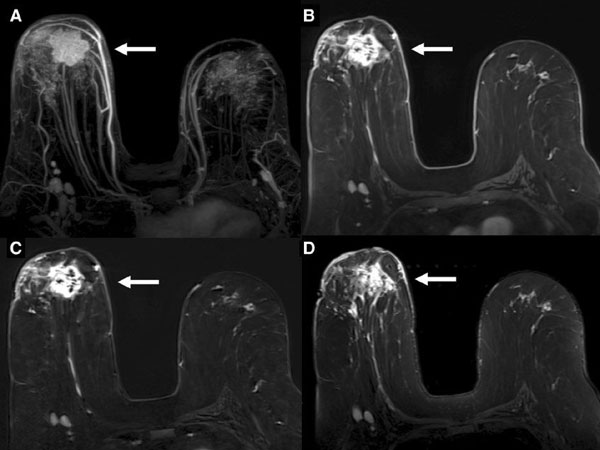

Contrast-Enhanced Mammography (CEM)